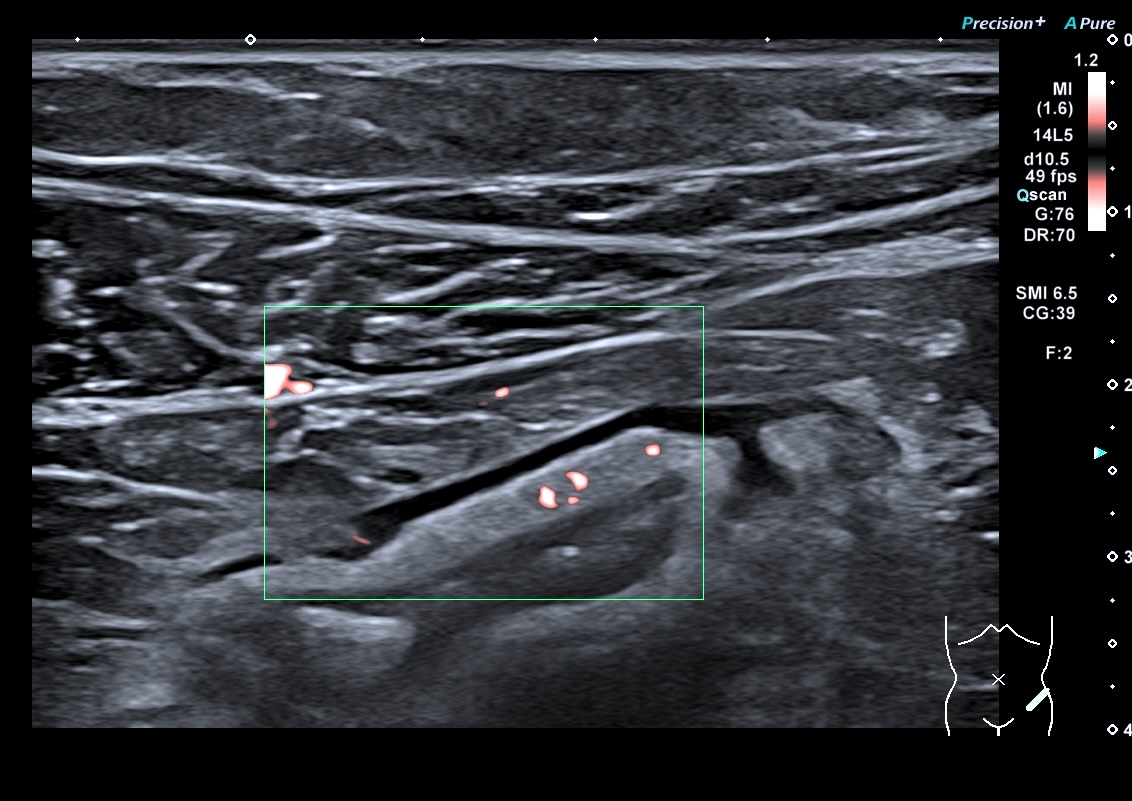

Sigmoïde coupes transversales et longitudinales et doppler haute fréquence

En doppler énergie

La graisse est peu infiltrée, Doppler plus marqué (Limberg 2 voir 3)

Le score de Milan est de (4,5 x 1,4+2)= 8,3 donc la maladie reste active, elle s'est même dégradée. (Score passé de 5.74 à 8.3)